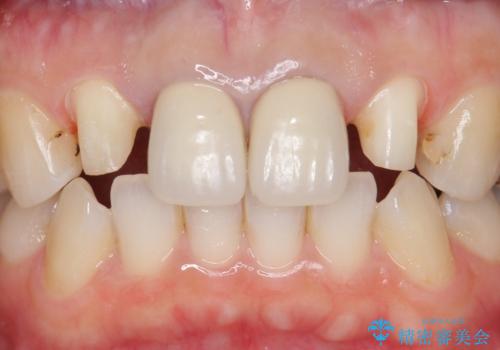

- 上顎の前から2番目の歯の古い樹脂をセラミックにしたいといらっしゃった方の症例です。

古い樹脂を除去後、オールセラミッククラウンによる補綴を行いました。